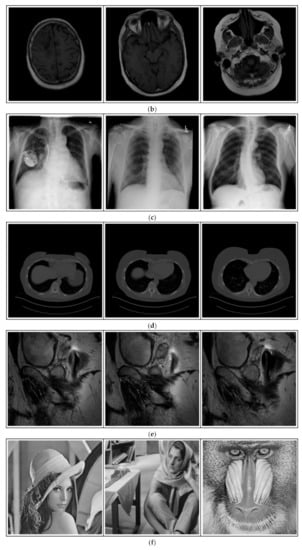

Breast-MRI-NACT-Pilot is an MRI-type image database, collecting breast medical images of 64 patients. Some samples are shown in Figure 12a.

Figure 12.

Sampled images in the tested benchmark databases: (a) Breast-MRI-NACT-Pilot (breast), (b) ACRIN-DSC-MR-Brain (brain), (c) NIH (chest), (d) Lung-PET-CT-Dx (lung), (e) Prostate-MRI (prostate), and (f) Other grayscale standard images.

- (b)

- ACRIN-DSC-MR-Brain database (available at: https://wiki.cancerimagingarchive.net/pages/viewpage.action?pageId=50135264 (accessed on 4 November 2021))

ACRIN-DSC-MR-Brain database contains MRI-type and CT-type brain medical images. Some samples are shown in Figure 12b.

- (c)

- NIH Database

ANIH is an X-ray type image database collecting chest medical images. Some samples are shown in Figure 12c.

- (d)

- Lung-PET-CT-Dx Database (available at: https://wiki.cancerimagingarchive.net/pages/viewpage.action?pageId=70224216 (accessed on 4 November 2021))

Lung-PET-CT-Dx is a CT-type image database collecting lung medical images. Some samples are shown in Figure 12d.

- (e)

- Prostate-MRI Database (available at: https://wiki.cancerimagingarchive.net/display/Public/PROSTATE-MRI (accessed on 4 November 2021))

Prostate-MRI database contains MRI-type medical images and collects prostate medical images. Some samples are shown in Figure 12e.

- (f)

- Other grayscale standard images

In order to investigate the flexibility of our method, we also tested several available images, as shown in Figure 12f.